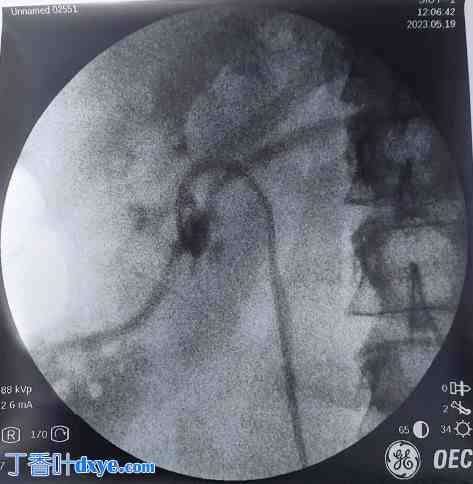

图4

术后X光片显示左肾结石已清除,DJ支架仍在原位。

顺行性左肾盂造影图,可见造影剂进入肾静脉。

患者插入肾造瘘管5小时后出现剧烈出血,随后导致低血压。患者被转至重症监护病房 (HDU) 进行复苏治疗。输注4单位血液和新鲜冰冻血浆 (FFP),患者的血流动力学得以稳定。进一步的放射影像学检查,特别是CT血管造影,显示肾造瘘管意外穿过左肾下极肾盏,到达左肾静脉,其尖端距离下腔静脉 (IVC) 开口仅2毫米(图5)。通过液体复苏和夹紧PCN管,患者病情得以稳定。